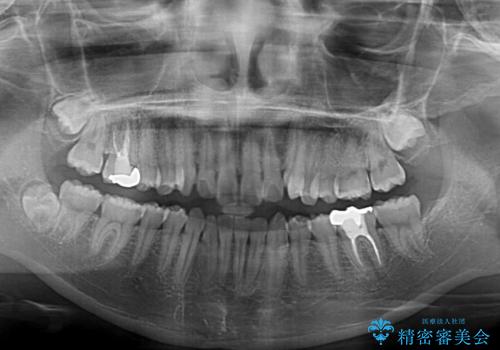

- 左右の八重歯を気にして来院された患者様です。

歯列としてはインビザラインでもワイヤー矯正でも対応できるものでしたが、インビザラインによる治療を希望されていました。

上顎の八重歯改善にインビザラインでは時間のかかってしまう可能性があり、更には口元が治療前よりも突出してしまう可能性があったため、補助装置により八重歯を事前に引き込んでおくことで、インビザラインによる治療をスムーズに行えるように計画しました。